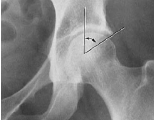

Q what is the name of this measurement? and what is the average + range?

A: Femoral Angle (Mikulicz’s Angle)

assesses the angle between the femoral shaft and neck. The normal range is 120-130°.

A: Skinner's Line

assesses the position of the femoral head relative to the greater trochanter.

Normal Finding: The fovea capitis should lie at or above the trochanteric line.